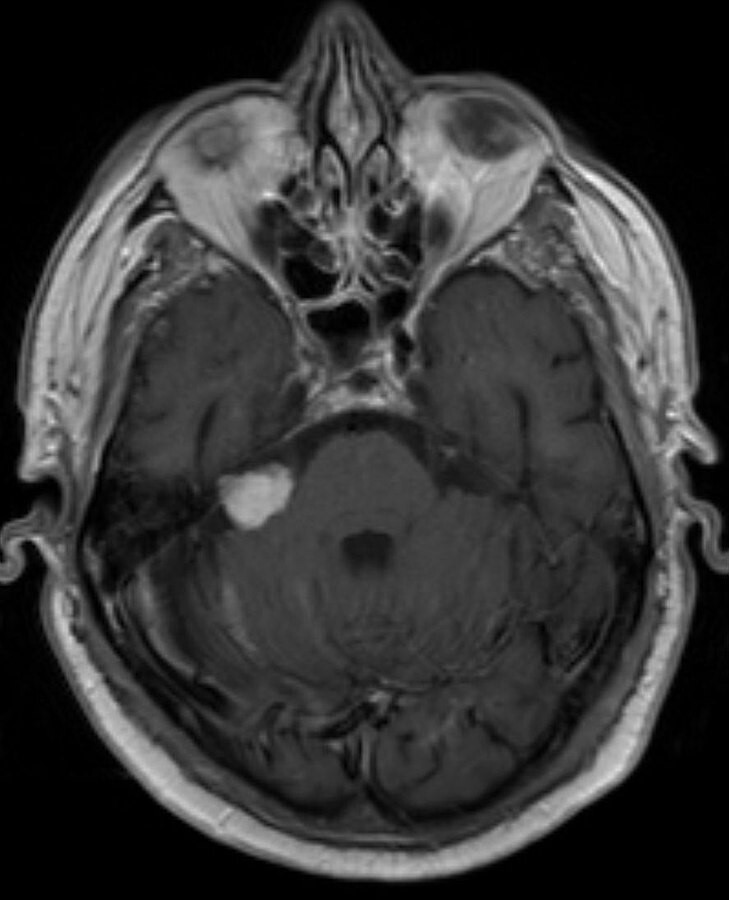

What can be seen on this MRI?

vestibular schwannoma (acoustic neuroma) of the right cerebellopontine angle